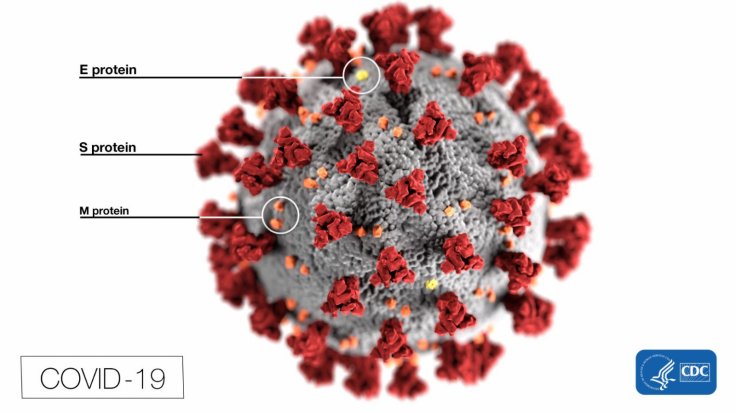

Spikes are protein structures that cover the surface of the SARS-CoV-2 virus. These structures enable the virus in infecting human cells, especially lung cells. ACE2 (Angiotensin-converting enzyme 2), an enzyme that is found on the cell membranes of cells in the lungs, intestines, arteries, kidneys and heart, is targeted by the spike.

Glycans are sugar compounds covering the surface of proteins. Much like all viral proteins, the SARS-CoV-2 spike protein has a thick layer of glycans on its surface. Attached to specific regions of the spike, they protect it from the immune system of the host. The authors tried to ascertain whether certain glycans decorating the SARS-CoV-2spike protein play an active role in the infection process.

It was discovered that glycans known as 'N-glycans' that are connected to the spike protein at two specific regions—N165 and N234—stabilized the change in the shape of the spike when its RBD was exposed, thereby, assisting in the infection process. RBD is the part on the spike that helps it latch on to receptors. The authors wrote: "We reveal an essential structural role of N-glycans at sites N165 and N234 in modulating the conformational dynamics of the spike's receptor-binding domain (RBD), which is responsible for ACE2 recognition."